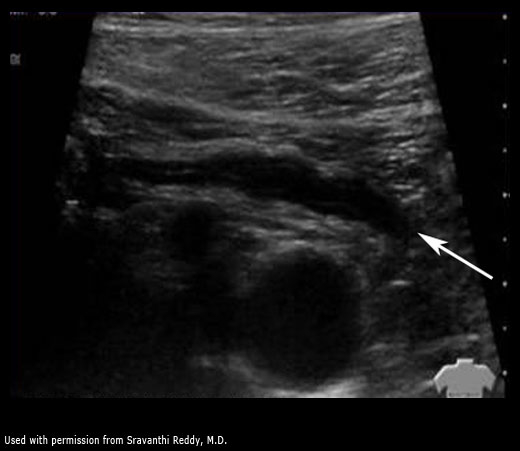

Normal appendix on ultrasound

If the wall is thickened > 6 mm OR an appendicolith is visualized in the appropriate clinical context, this is diagnostic of appendicitis

Remember that US is the study of choice for diagnosis in pregnant patients and children.